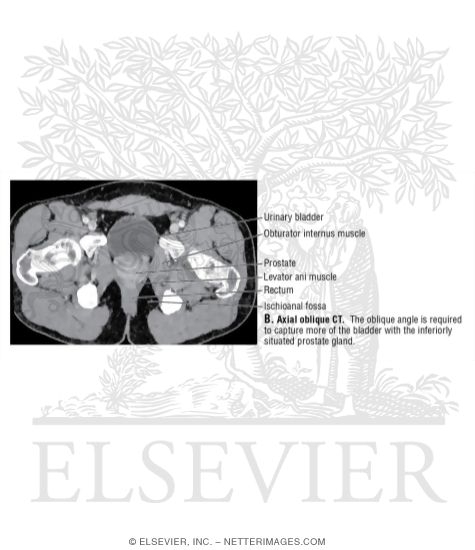

Bladder-Prostate Junction: Axial Oblique CT

Labeled-Cochard Imaging 1E Radiographs